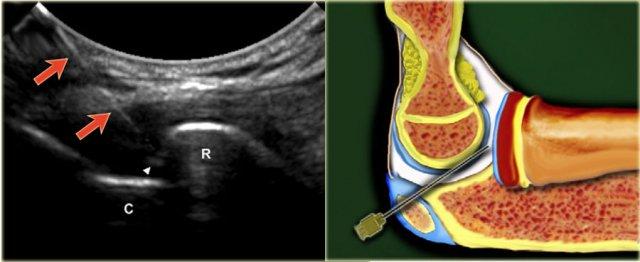

Elbow

Để tiêm khớp khuỷu tay, bệnh nhân nằm ngửa với cánh tay gấp 90°, được nâng lên và đặt trên gối. Khe khớp giữa chỏm quay và chỏm con có thể dễ dàng sờ thấy. Bàn tay ở tư thế sấp hoặc có thể xoay về tư thế ngón cái hướng lên, tư thế này cần thiết để mở khớp tối đa.

Đầu dò được đặt trên khớp để hiển thị khoang khớp. Kim (cỡ 22, dài 30 mm) được hướng theo góc đầu-đuôi nhẹ ở phía lưng-ngoài của khớp về phía khoang khớp, nhắm đến bề mặt khớp của chỏm quay.

Khi thấy kim đã vào trong khớp và cảm nhận được sụn của chỏm xương quay, kim được rút lui nhẹ để đảm bảo rằng vát kim không chạm vào sụn và hướng vào trong khớp.

Tiêm 5-8 mL thuốc cản quang. Không được cảm thấy có sức cản khi tiêm.